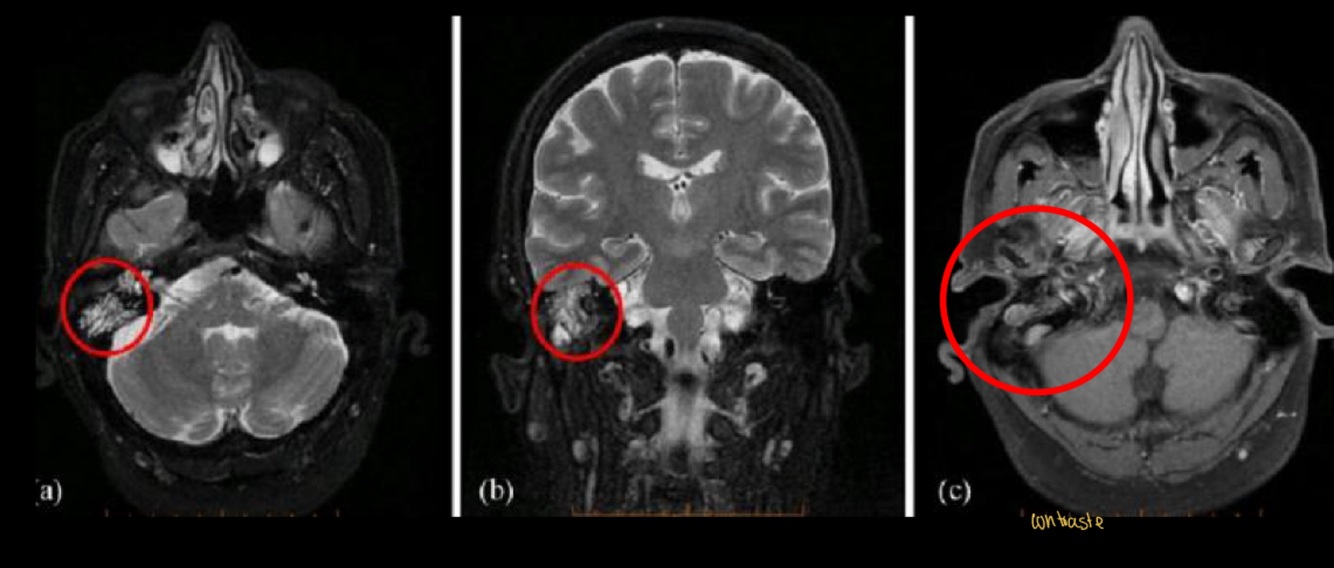

Diagnóstico probable

A

Otitis media

La RM está indicada en las complicaciones de la otitis media, ¿Coque veras en la secuencia T1 y T2?

T1: masa hipointensa en oído medio

T2: masa híper intensa en oído y mastoides